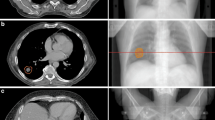

Fifth, plans were checked for all boundaries as defined above prior to individual RTQA (Fig. 2). In cases where the dose constraints were violated at a chosen number of fractions, planning iterations with a higher number of fractions up to a specified maximum of 12 fractions were performed. Prescribed doses and dose constraints were recalculated to the EQD2 using the respective α/β ratios of tumor and OAR, and aiming to deliver iso-effective doses to the tumor with lower toxicity by protracted dose delivery. If the normal tissue constraints could not be fulfilled by increasing the number of fractions to the maximum number, SBRT was not given but conventionally fractionated treatment performed instead. Sixth, we excluded lesions with large absolute PTVSIP volumes, with very small PTV as well as for single fraction radiosurgery from the use of the SIP concept. Seventh, we required high-precision patient positioning, motion management, and IGRT for the use of the SIP concept.

a The planning target volume (PTV, (light pink) intersects with planning risk volume (PRV, green) and organs at risk (OAR), small bowel (orange), in a patient with recurrent pancreatic cancer after resection. b The PRV is subtracted from PTV to define PTVdom (yellow). c The PTVSIP is defined as the intersecting region of PTV with the PRV (PTV ∩ PRV; magenta). d,e An intensity-modulated radiotherapy (IMRT) plan is developed to deliver full dose according to ICRU to PTVdom and a lower dose to PTVSIP respecting the dose constraints for small bowel in 12 fractions (Dmax = 47.4 Gy, D0.5ml = 44.5 Gy, D5ml = 44.4 Gy). Isodose levels as stated on the left side. f Relative dose–volume histogram (DVH). Protection of the 9.2 ml PTVSIP (left solid) compared with PTV (middle solid), ITV (bold dotted) and with PTVdom (right solid); gut (dashes). g Absolute DVH respecting the constraints for gut

Examples for a simultaneous integrated protection (SIP) for the optic nerve, the brainstem, and the brachial plexus with dose parameters in Supplementary Table 2. a Axial planning CT of a patient with sinonasal squamous cell carcinoma who was treated with chemoradiotherapy after positive margin resection at the left optic nerve. As she refused left orbital exenteration, PTVdom is treated with 64.8 Gy in 36 fractions. A 0.4 ml SIP volume is employed to respect a 60 Gy constraint to the left optic nerve. b The coronal plane visualizes the yellow 61.5 Gy isodose line around the nerve. c Absolute dose–volume histogram (DVH). d Axial and e sagittal planning CT of a patient with undifferentiated main nasal cavity carcinoma with initially direct contact to the brainstem which was shifted dorsally. Tumor shrinkage after two courses of induction chemotherapy with paclitaxel/cisplatin, then chemoradiotherapy with SIP-IMRT to 54 Gy during phase 1 followed by an adaptive sequential boost (not shown) during phase 2. f Isodoses at the interface between the PTV and the brainstem. g The brainstem constraint of 53 Gy is met as shown in the absolute DVH. h–j Hippocampus protection. h Delineation of the right (sky blue) and left (blue-green) hippocampus with the respective PRVs (yellow) that are generated by a 7 mm isotropic margin to the hippocampi. PTVSIP corresponds to the PRV of the hippocampus minus the hippocampus itself (PTVSIP = PRV[side]\hippocampus[side]). i A total dose of 35 Gy in 14 fractions was prescribed to the PTVdom. Note the 28.0 Gy (green) and the 17.5 Gy (cornflower blue) isodoses at the two SIP volumes. j In the absolute DVH, the hippocampi receive a mean dose of ≤10 Gy. PRV planning risk volume, PTV planning target volume